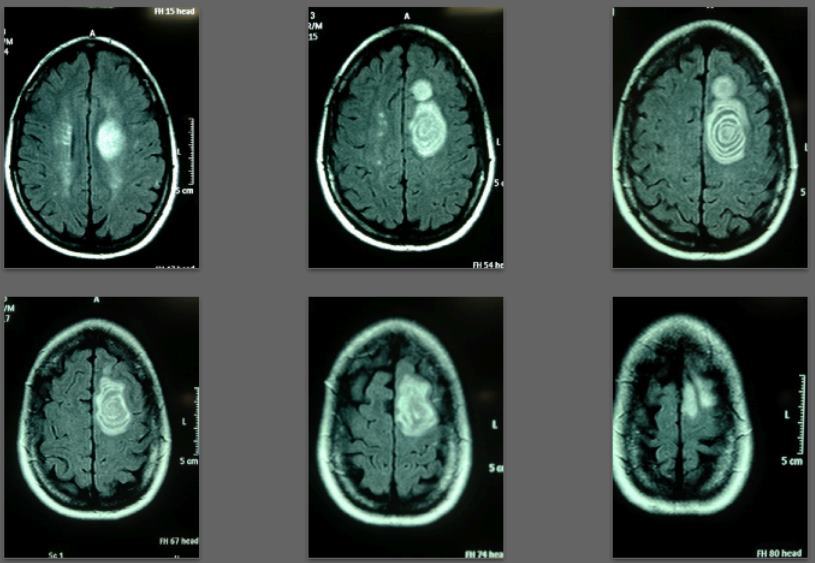

Specifically: Recent lesions appeared partially repaired or disappeared on MRI scans after one and two years of treatment.

Before/after MRI images for one of 1,000+ patients of Dr. Coimbra

PDF is attached at the bottom of this page

2008 Convulsive seizures Diagnosis: Balo’s concentric hemiparesis

Starting daily dose 25,000 IU; increased in stages to 80,000 IU on October 28, 2010. Asymptomatic since 2010.

2008 MRI

2013 MRI